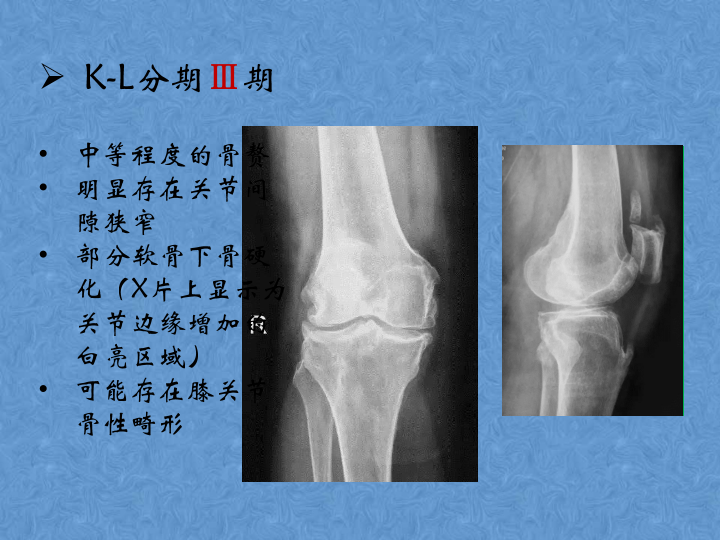

骨关节炎的阶梯治疗